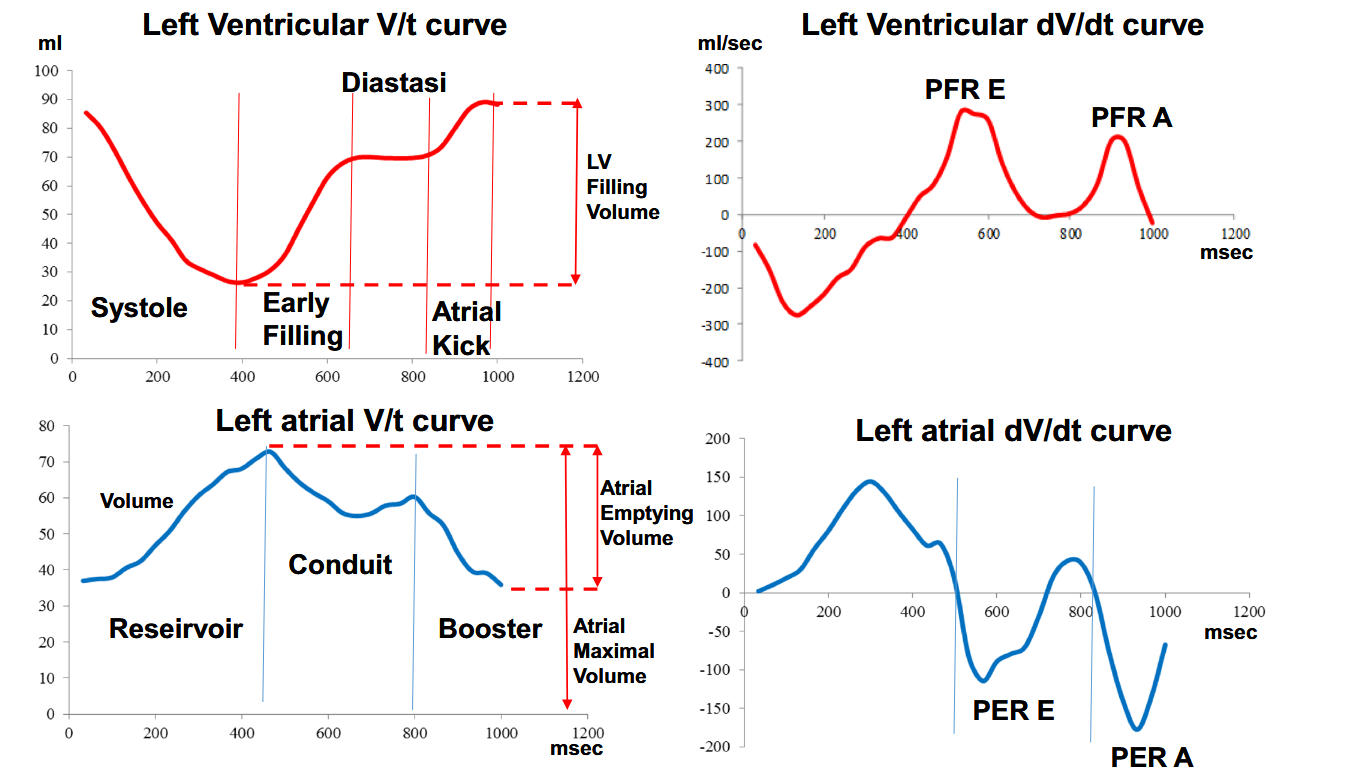

After deriving the atrial and ventricular dV/dt curves from the volume curves. Peaks of the ventricular dV/dt curves were defined as follows: the first positive peak was defined as the early peak filling rate (PFR-E) and the second peak was defined as atrial peak filling rate (PFR-A). PFR-E and PFR-A represent the maximum speed of passive filling and the maximum speed of filling secondary to atrial contraction, respectively. Between the two peaks, a zone of almost zero speed is normally present; this is the phase of diastasis.